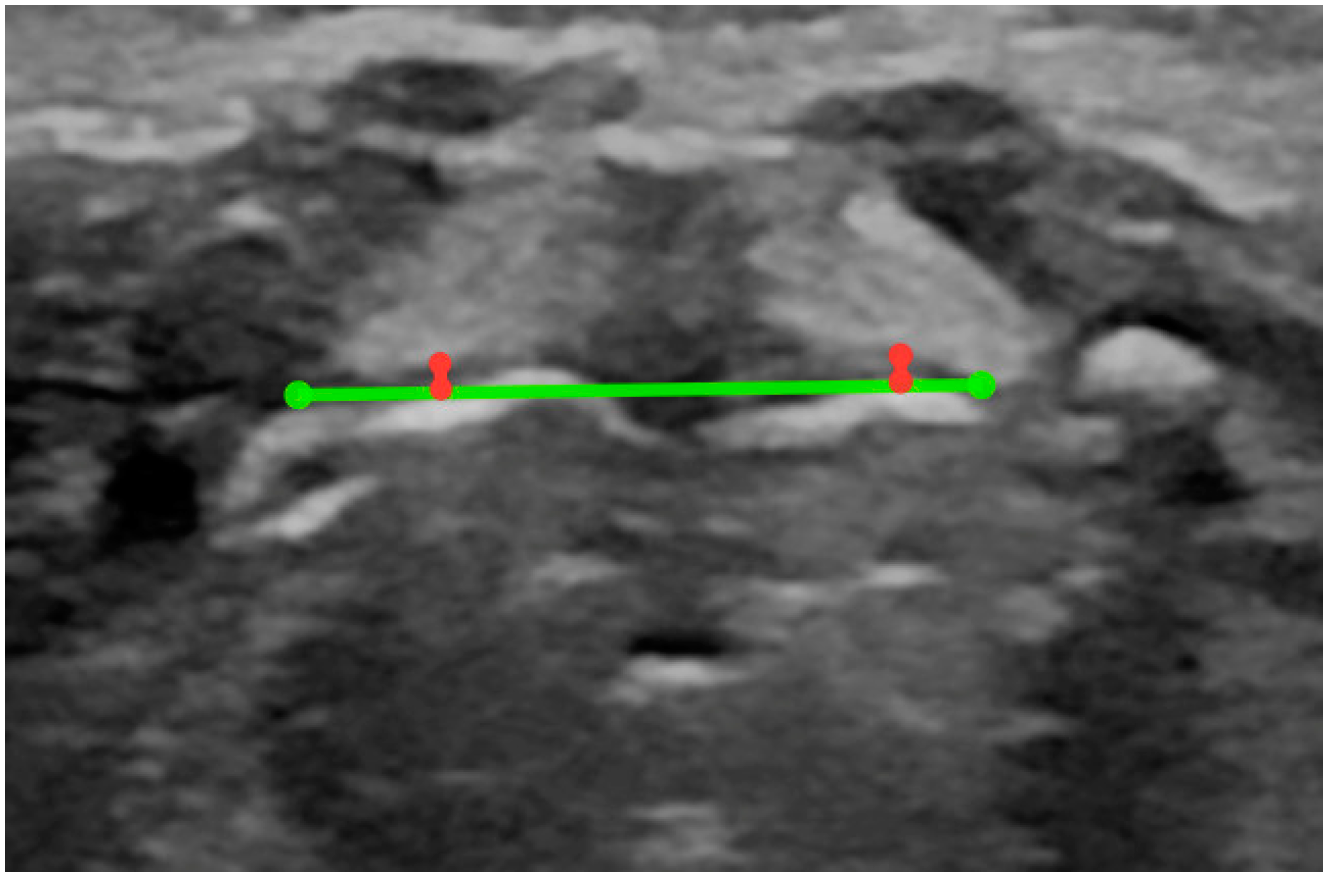

- Width of the larynx at the level of the glottis (measurement taken in the transverse plane from the external margins of the thyroid cartilage) (Figure A2);

- Depth of the larynx at the level of the glottis (measurement taken in the transverse view from the external margin of the thyroid cartilage to the external border of the annular cartilage) (Figure A2);